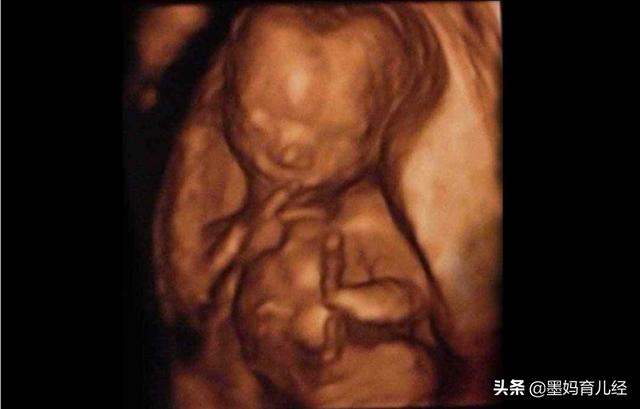

在怀孕4个月的时候胎宝宝的身长约为10-16cm,胎重约25-110g,此时胎宝宝也早已发育“成形”了,胎宝宝的发育也相对稳定了一些,此时妈妈们也会进入到一个比较舒适的阶段。

怀孕4个月妈妈肚子不疼也没有不舒服的症状普遍来说都是非常正常的,在怀孕四个月孕吐反应消失了,尿频也有所缓解了,再加上此时胎宝宝还比较小,妈妈还感觉不到宝宝的胎动,如果此时还没有显怀,妈妈就更感觉不到宝宝的存在了,如果妈妈在12周的时候已经做了一次检查,结果是正常的,妈妈就不用太过担心。